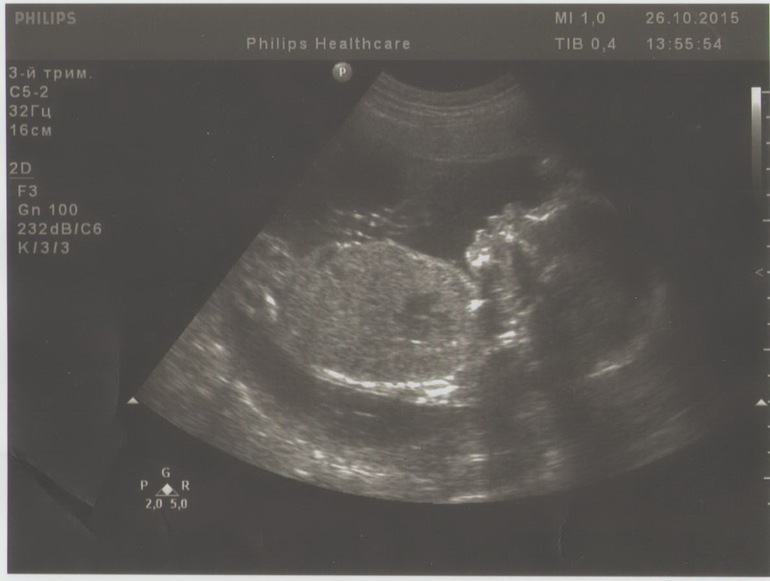

Пошли на повторное узи проверить как поднимается плацента и проверка отсутствия шумов в водах. Муж пошел со мной, хоть и опоздал, ехал сам, но прилетел и успел вовремя - моя очередь задержалась на пол часа. И мне коварно удалось его заманить в кабинет... хихихи.. А он не хотел... стрёмно ему было! И ойййй, видели бы вы его лицо.

Я когда уехала в Херсон на 2 недели, а там сильно вырос живот, было что-то похожее. Уезжала, говорит, такая чуть-чуть беременная, а вернулась с таким пузенем))) Просил не требовать реакции, дать ему пару дней на адаптацию) А после узи ему подарили фотокарточку, и он сразу сказал, что у Кузи мой нос)))) Я вот дома присмотрелась, и поняла, что губки папины) Вот думаю, пол дня прошло, когда он уже отреагирует?))

Кстати, 2-е узи подряд ставят срок по развитию плода на неделю больше. Я, правда, именно в том месяце М не отметила))) и везде говорю наугад 30 мая, хотя, может, М пошли и дня на 3 раньше.... Но некоторые показатели больше реально на неделю! Врач говорит, что реальный срок можно определить только на 8-9 неделе.

Так мне нравится смотреть на малыша)))) Такая радость, что не насмотреться)

У нас... МАЛЬЧИК!!! с явно выраженным мужским кладом))))))